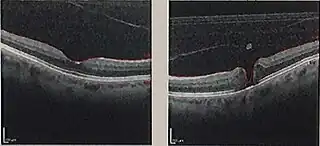

![]() Tomografía de coherencia óptica de un agujero macular (derecha), comparado con una mácula normal | ||

La exploración oftalmológica hace posible establecer el diagnóstico. Existe una prueba denominada tomografía de coherencia óptica (OTC) que permite obtener imágenes de gran precisión, mediante las cuales se puede averiguar el grosor de la retina, la presencia de agujero macular y su grado de evolución.